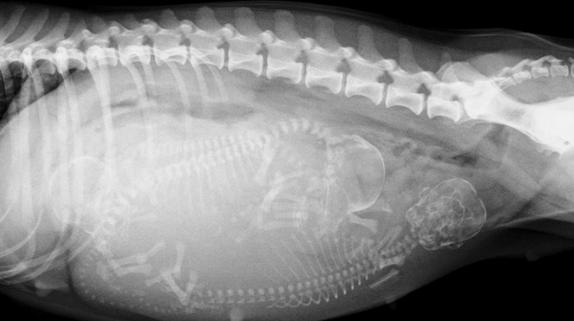

有经验的兽医通过轻轻触摸猫咪的腹部可以在怀孕17-25天时摸到怀孕后子宫内出现的孕囊。但更精确的判断就需要拍摄X线片及做B超检查了哦。

约在怀孕43-45天后拍摄X线片可以明显的看到小猫的骨骼~(请放心这时的X线片是不会对怀孕猫咪及小猫造成伤害的)。而约20天时,通过B超检查探测到的小猫心室的跳动也是它们在告诉你“我很好~!请不要担心我!”